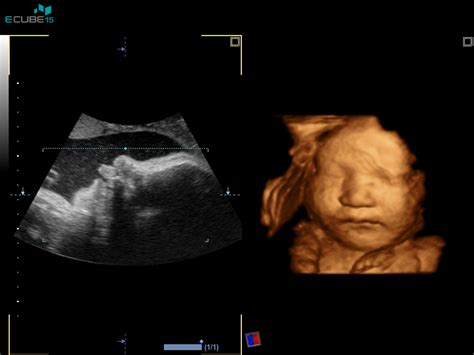

Primer Barbare, 30-letne nosečnice v 30. tednu prve nosečnosti, izpostavlja to nenavadno izkušnjo. Pred približno desetimi dnevi je zvečer, tik pred ali med gibi otročka, prvič zaslišala "pok" ali "tlesk", ki ga je primerjala s "tleskom" sklepa odraslega človeka ali s "tleskom" nohta ob noht. Ta zvok se je ponavljal in postajal vse pogostejši, saj je bil otrok vsak dan zelo aktiven. Barbara se je spraševala, ali je možno, da bi že tako majhnemu otročku med gibi "pokali" sklepi, ali bi lahko šlo za kakšno okvaro gibalnega sistema.

Ginekolog mag. Stanko Pušenjak je v svojem odgovoru priznal, da omenjenega pojava ne pozna, a hkrati ni izključil možnosti, da gre za nekaj, na kar namiguje nosečnica. Svetoval je opravljanje orientacijske preiskave s posebno pozornostjo na plodov skeletni sistem. Kot je pojasnil, bi ga, če bi se dogajalo kaj bolečega za plod, pričakoval, da bi obmiroval in se ne bi več tako intenziovno gibal, saj bi poškodbe sklepov in kosti ob gibanju bolele bolj kot ob mirovanju.

- Gibanje sklepov ploda: Čeprav je težko potrditi, da bi že v tako zgodnji fazi nosečnosti sklepi ploda povzročali slišne "pokove", je to ena od možnosti. S staranjem in razvojem ploda se sklepi premikajo v različne položaje. V nekaterih primerih bi lahko trenje ali premik v sklepu, še posebej če je plod obrnjen na določen način, povzročilo zvok. Vendar pa, kot je poudaril dr. Pušenjak, bi boleče stanje verjetno vplivalo na aktivnost ploda.

- Gibanje amnijske tekočine: Amnijska tekočina, ki obdaja plod, je tekočina, ki se premika. V nekaterih primerih bi lahko hitri gibi ploda povzročili valovanje ali premikanje te tekočine, kar bi lahko ob določenih pogojih ustvarilo zvok, podoben "pokanju".

- Zvočni pojavi, povezani s položajem: Položaj ploda v maternici in položaj maternice lahko vplivata na to, kako se zvoki prenašajo. Ko je otrok v določenem položaju, bi lahko njegovi gibi ali premikanje amnijske tekočine ustvarilo bolj izrazite zvoke. Barbara je kasneje opazila, da se "tleski" redkeje pojavljajo, ko otroček ni več v medenični vstavi, kar bi lahko nakazovalo na povezavo z lego.